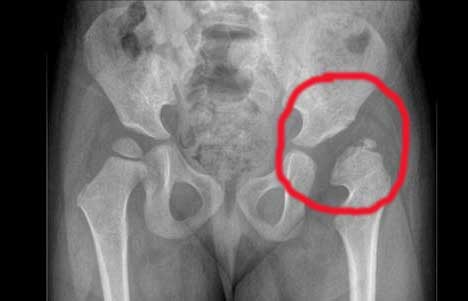

Чем раньше диагностирована патология, тем быстрее и успешнее проходит терапия. Обнаружить недоразвитость позволяют внешний осмотр, жалобы родителей, проведение функционального тестирования. Подтвердить диагноз помогают результаты ультразвукового, рентгенологического исследований. Хотя рентгенография считается самым информативным методом, ее проведение противопоказано детям до 3 месяцев. Степень зрелости ТБС устанавливается по параметрам ультразвуковой классификации Графа. Например, тип 2а по Графу – это незрелый диспластичный сустав.

| Диспластические изменения проксимального отдела бедренной кости | Такая врожденная форма недоразвития выявляется при измерении шеечно-диафизарных углов. Параметр рассчитывается по линиям, объединяющим центры шеек и головок костей, и диафизарным линиям. У детей старше 3 месяцев недоразвитие бедренных головок устанавливается по рентгенографическим изображениям |